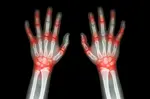

Rheumatoid arthritis is a disease of the joints, usually the smaller joints in the body. Not always a disabling condition, it can be controlled with medicine.